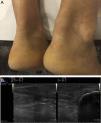

Presentación del caso clínicoVarón de 59 años exfumador, hipertenso y con hipercolesterolemia de larga evolución tratada con estatinas, aunque con escasa adherencia. Cardiopatía isquémica que comienza como IAMSEST Killip II hace un año, con enfermedad coronaria de 3 vasos que precisó de revascularización quirúrgica con cuádruple bypass. Varios familiares de primer grado presentaron cardiopatía isquémica prematura e hipercolesterolemia. En la exploración física no presentaba arco corneal ni xantelasmas, y sí engrosamiento de los tendones Aquiles y presencia de xantomas tendinosos en los nudillos de ambas manos (fig. 1A, fig. 2A). No tenía soplos cardiacos ni carotídeos. Obesidad troncular (talla 1,78m, peso 97,5kg, IMC 30,8kg/m2, perímetro de cintura 108cm), PA: 120/65mmHg, no visceromegalias. Pulsos distales palpables y simétricos.

Se solicita una ecografía para evaluar los xantomas, que objetivó engrosamiento de los tendones Aquiles (D>I)2 con pérdida de su estructura fibrilar homogénea, con un área en su interior en el tercio medio hipoecoica, compatible con xantomas a este nivel3,4. Así mismo se observa la misma imagen ecográfica en varios tendones extensores de las manos (fig. 1B, fig. 2B).